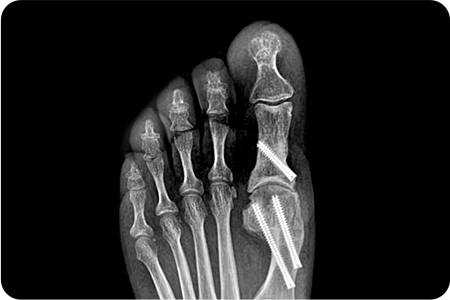

무지외반증 수술 적용사례

1

최소침습

무지외반증 수술

엄지발가락 부위에 약 2~3mm 크기의 작은

구멍을 만들고 특수한 미세 절삭 기구를 사용해

변형된 뼈를 절골하여 올바르게 교정합니다.